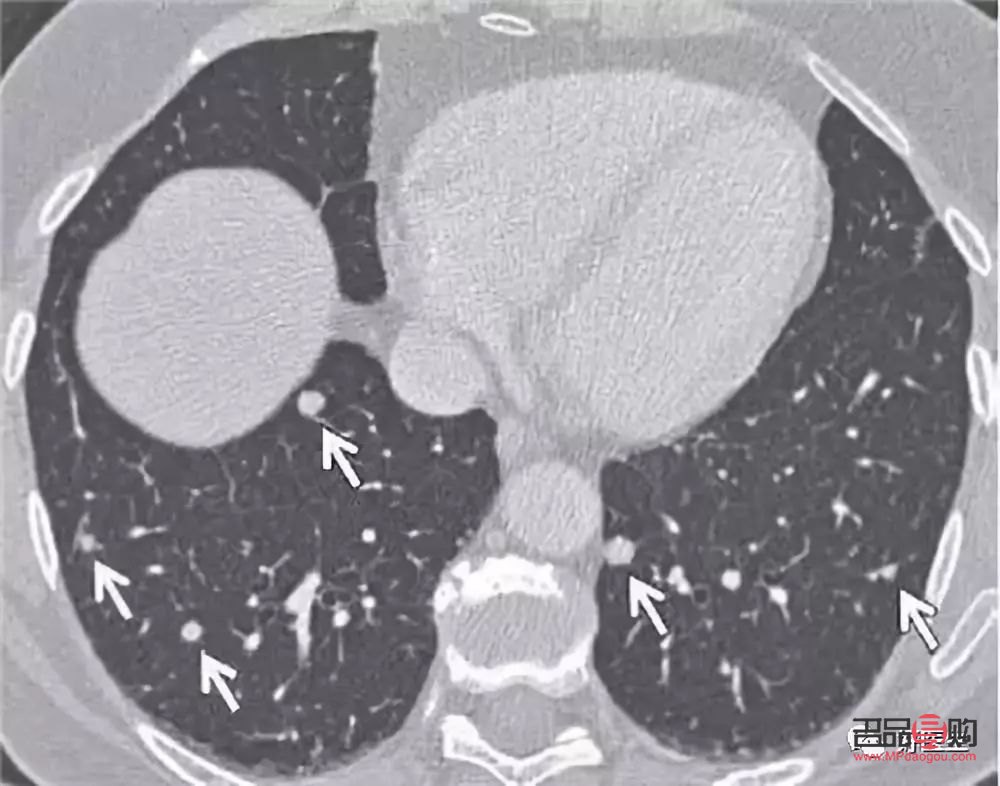

導(dǎo)讀: 肺結(jié)節(jié)是指在肺部影像學(xué)檢查中發(fā)現(xiàn)的直徑小于3厘米的圓形或類圓形陰影,它可能是良性的,也可能是惡性的,不論其性質(zhì)如何,一旦發(fā)現(xiàn)肺結(jié)節(jié),合理的身體護(hù)理都至關(guān)重要,下面,我們將為您詳細(xì)介紹肺結(jié)節(jié)后的身體護(hù)理...

肺結(jié)節(jié)是指在肺部影像學(xué)檢查中發(fā)現(xiàn)的直徑小于3厘米的圓形或類圓形陰影,它可能是良性的,也可能是惡性的,不論其性質(zhì)如何,一旦發(fā)現(xiàn)肺結(jié)節(jié),合理的身體護(hù)理都至關(guān)重要,下面,我們將為您詳細(xì)介紹肺結(jié)節(jié)后的身體護(hù)理方法。